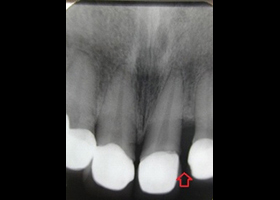

1.術前口內正面照、局部X光片。

proimages/case/cosmetic/pic_case-020.jpg

proimages/case/cosmetic/pic_case-021.jpg